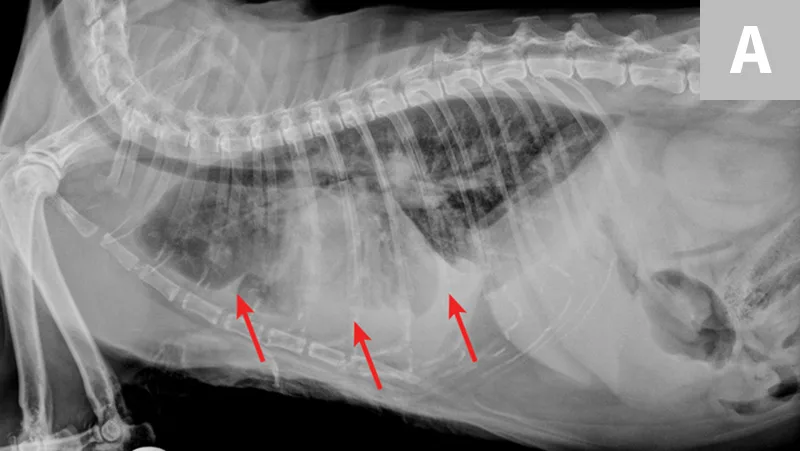

Overt cardiomegaly may be understated on radiographs because of changes in internal diameter that do not affect the overall cardiac silhouette. Vertebral heart score >9.3 supports a CHF diagnosis.1 Pulmonary venous congestion can be absent, and pulmonary arterial distension may be appreciated. The presence of pleural effusion with simultaneous pulmonary infiltrates is supportive of CHF (Figure 1).2

Congestive heart failure. Note the pleural effusion (arrows).